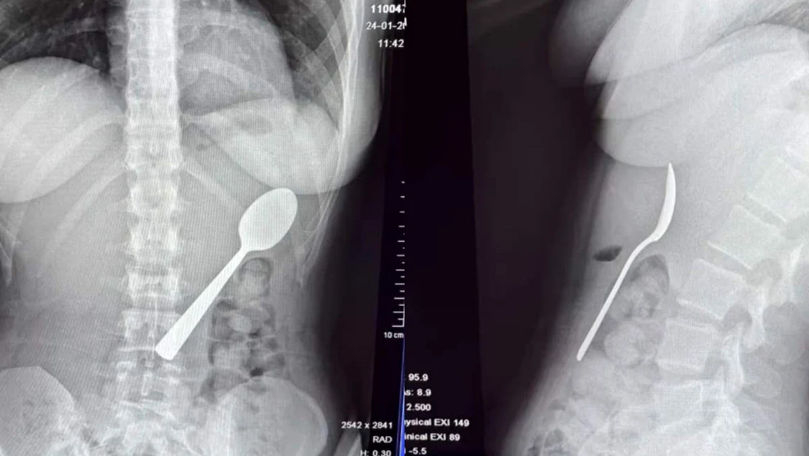

O femeie de 28 de ani din Belgia a trăit momente terifiante după ce a înghițit accidental o lingură de 17 centimetri. Incidentul s-a produs în timp ce mânca iaurt pe canapea, iar totul a pornit de la o reacție neașteptată a câinelui ei, un energic Hungarian Vizsla pe nume Marley.

Medicii au decis să îi îndepărteze lingura sub anestezie locală, evitând o operație deschisă. Procedura a fost delicată, necesitând rotirea lingurii în interiorul stomacului pentru a putea fi extrasă în siguranță.